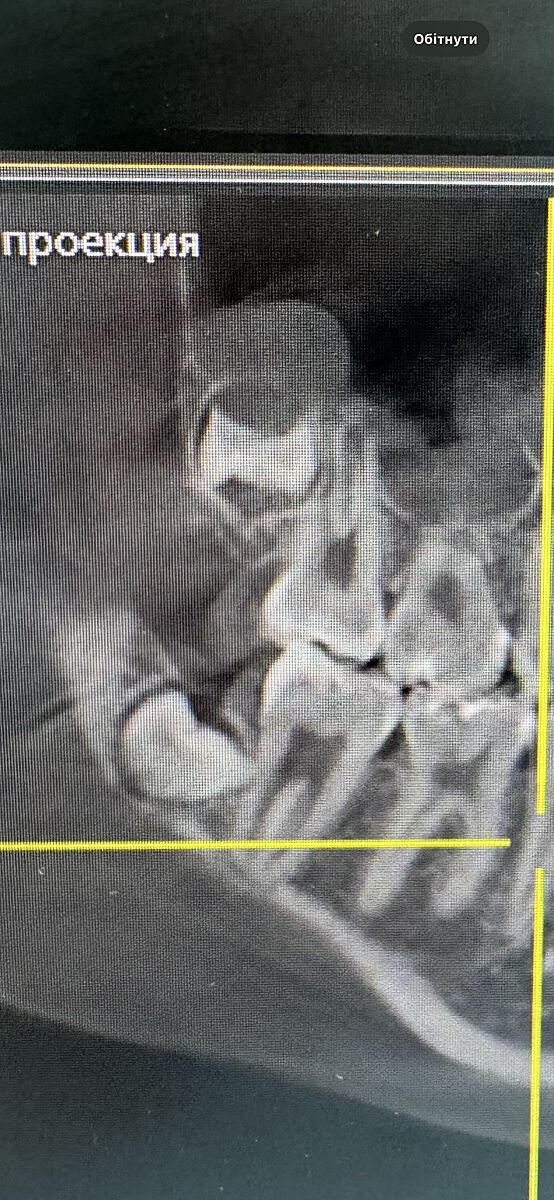

Видаляти зуби мудрості? Фото КТ дитини. Чому ортодонти так хочуть позбутись їх?

В доньки вирівняні зуби брекетами, 14 років

Ортодонт каже треба рвати через 6 міс всі 4 зуба мудрості, поки немає в них коріння, щоб потім не поїхав зубний ряд

Як на мене то верхні зуби ростуть вниз, не заїжджають на сусідні

у вас прямі покази на виривання вони вже прям впираються в зуби

ряд точто поїде як не прибрати